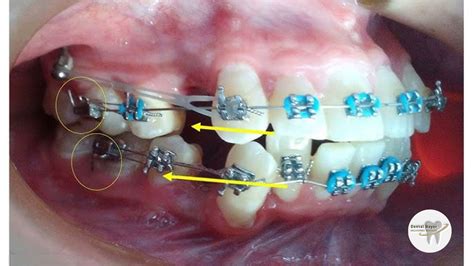

Las cadenetas en ortodoncia, también conocidas como cadenetas elásticas para brackets, son dispositivos compuestos por una serie de eslabones elásticos unidos, que se insertan entre los brackets para aplicar una fuerza continua y constante.

Su principal función es cerrar espacios entre los dientes, ya sean producto de extracciones o de diastemas, y ayudar en la alineación y rotación de piezas dentales para conseguir el movimiento deseado.